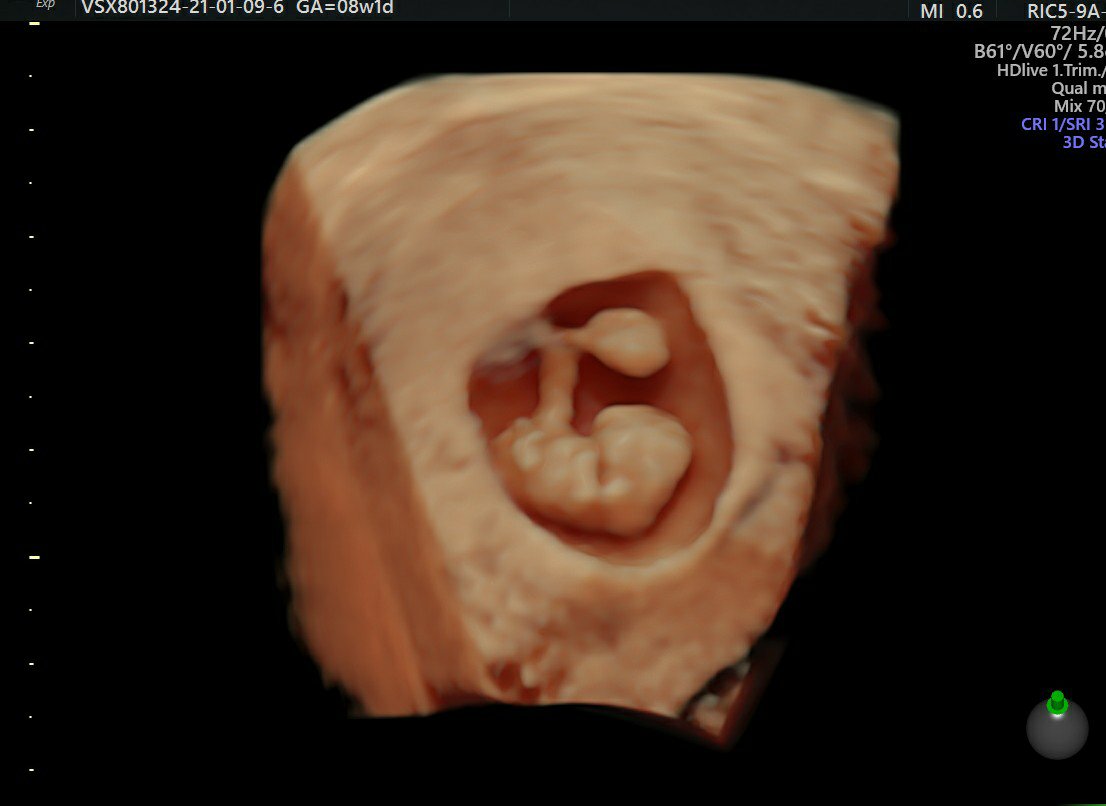

Usg z soboty dzidziuś ma 1,7cm

Taki piękny robaczek już dziś to mamy 8tydz+3dni.

Image_6~2.jpeg